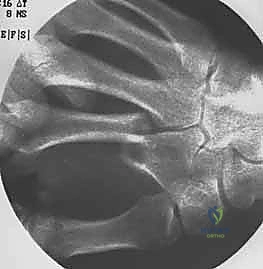

معرض الصور الشعاعية: تقييم النتائج الجراحية (Post-Op X-rays)

النجاح الحقيقي يُقاس بالاستعادة المثالية للشكل التشريحي للعظم. توضح هذه الصور الشعاعية بعد الجراحة الدقة المتناهية في إعادة محاذاة العظام وتثبيتها.

التثبيت المحكم يسمح بالشفاء العظمي الأولي (Primary Bone Healing) دون تكوين كتلة عظمية كبيرة (Callus) قد تعيق حركة الأوتار المنزلقة فوقها.

- الأشعة السينية (X-rays): يتم أخذ صور من زوايا متعددة (أمامية خلفية، جانبية، ومائلة) لتحديد موقع الكسر، نوعه (عرضي، حلزوني، مائل، متفتت)، ودرجة التزوي (Angulation).